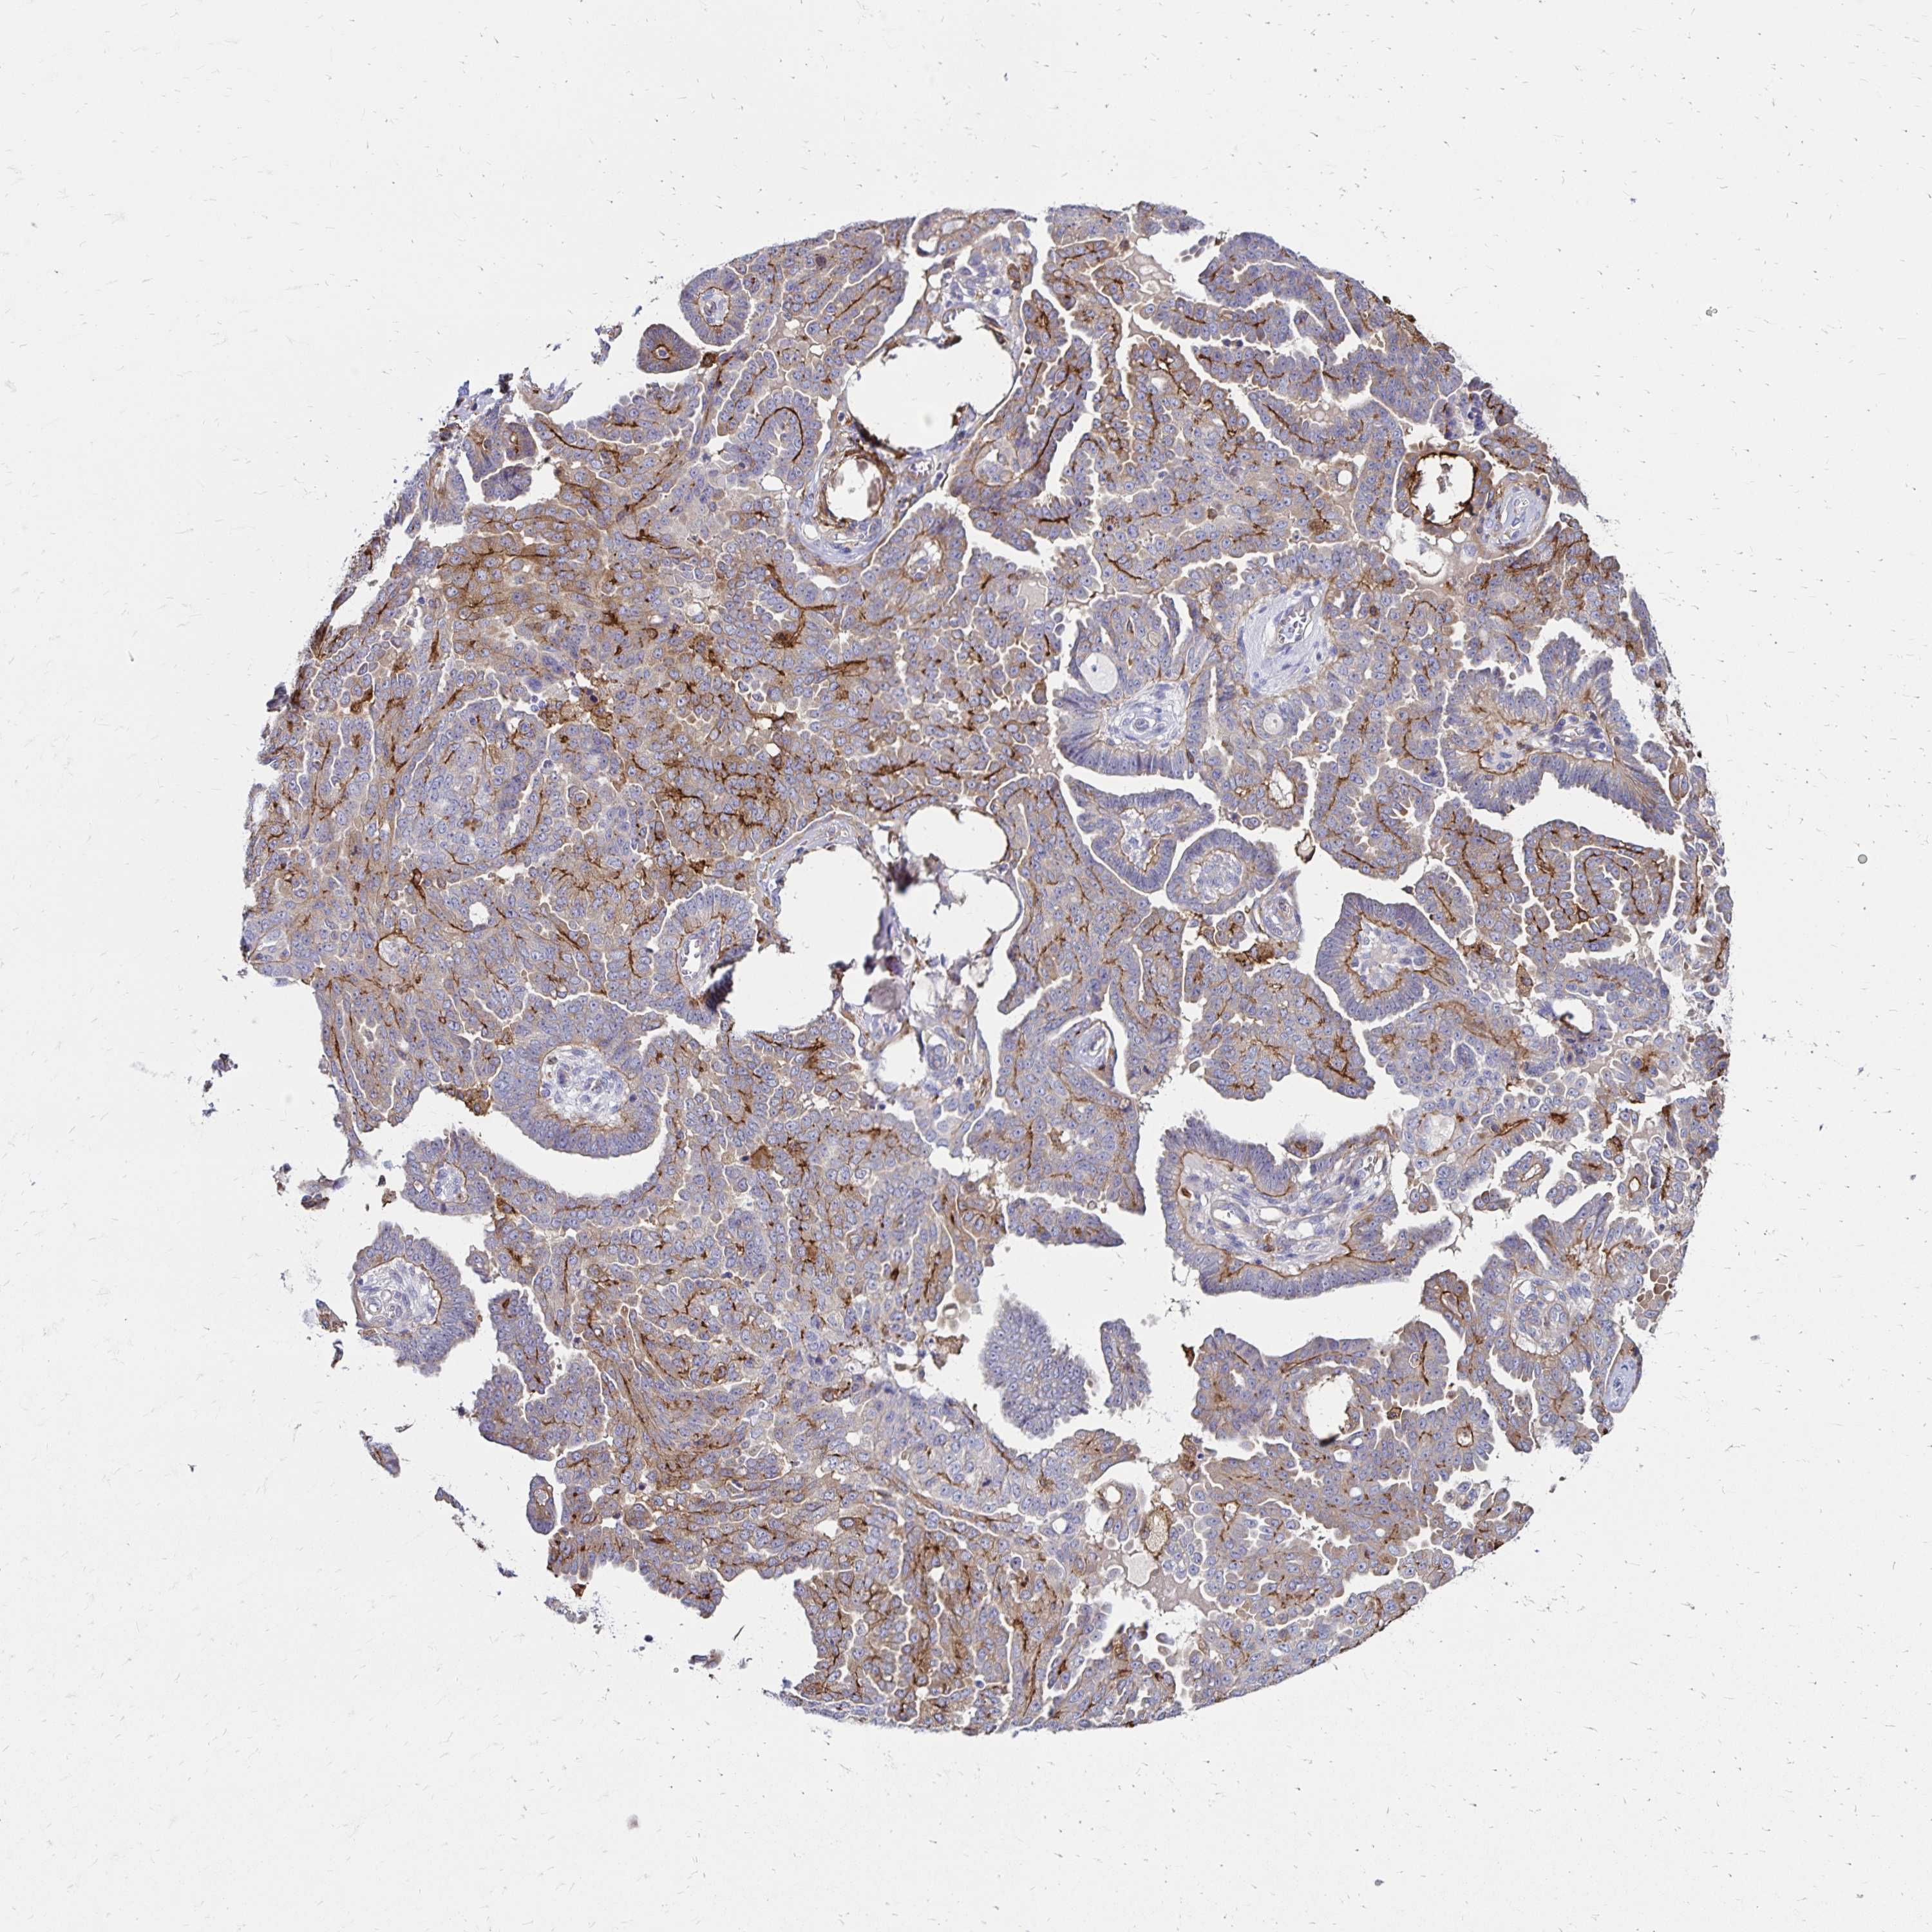

OVARIAN CANCER - Protein expressioni

A mouse-over function shows sample information and annotation data. Click on an image to view it in a full screen mode. Samples can be filtered based on level of antibody staining by selecting one or several of the following categories: high, medium, low and not detected. The assay and annotation is described here.

Note that samples used for immunohistochemistry by the Human Protein Atlas do not correspond to samples in the TCGA dataset.

Antibody stainingi

Antibody staining in the annotated cell types in the current human tissue is reported as not detected, low, medium, or high, based on conventional immunohistochemistry profiling in selected tissues. This score is based on the combination of the staining intensity and fraction of stained cells.

Each image is clickable and will lead to virtual microscopy that enables deeper exploration of all samples and also displays staining intensity scores, fraction scores and subcellular localization as well as patient and tissue information for each sample.

Antibody HPA055338

Antibody HPA056015

Staining

High

Medium

Low

Not detected

Intensity

Strong

Moderate

Weak

Negative

Quantity

>75%

75%-25%

<25%

None

Location

Nuclear

Cytoplasmic/membranous

Cytoplasmic/membranous,nuclear

Cystadenocarcinoma, serous, NOS

Cystadenocarcinoma, mucinous, NOS

Carcinoma, endometroid